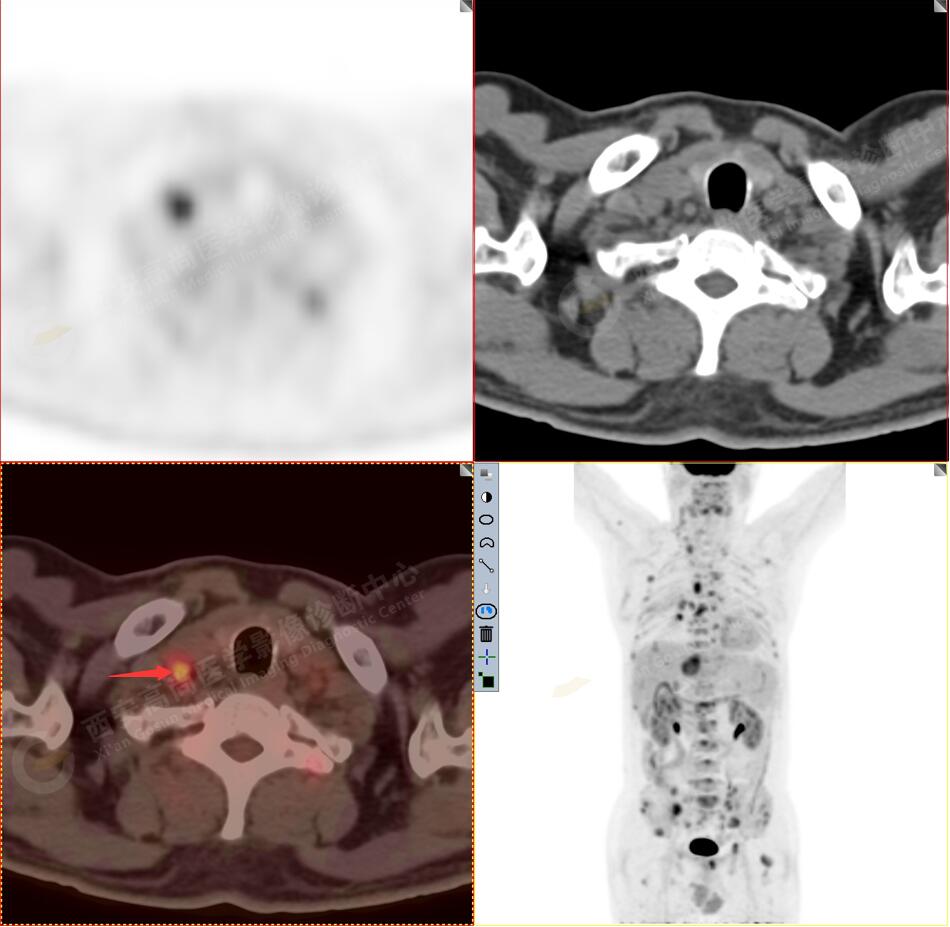

2.以下為全身多發(fā)轉移灶

3.右側頸部(Ⅱ-Ⅴ區(qū))、右側腋窩區(qū)、右側肺門及縱隔(1R、1L、2、4、6、7組)、肝門區(qū)多發(fā)腫大淋巴結,呈不同程度異常增高,均考慮為淋巴結轉移。

5.右側肱骨上段、左側肩胛骨、右側鎖骨胸骨端、胸骨、雙側多發(fā)肋骨、脊柱多發(fā)椎體及附件、雙側髂骨、雙側髖臼、雙側恥骨、雙側肱骨上段多發(fā)成骨性病變,呈不同程度FDG代謝異常增高,考慮為多發(fā)骨轉移瘤。